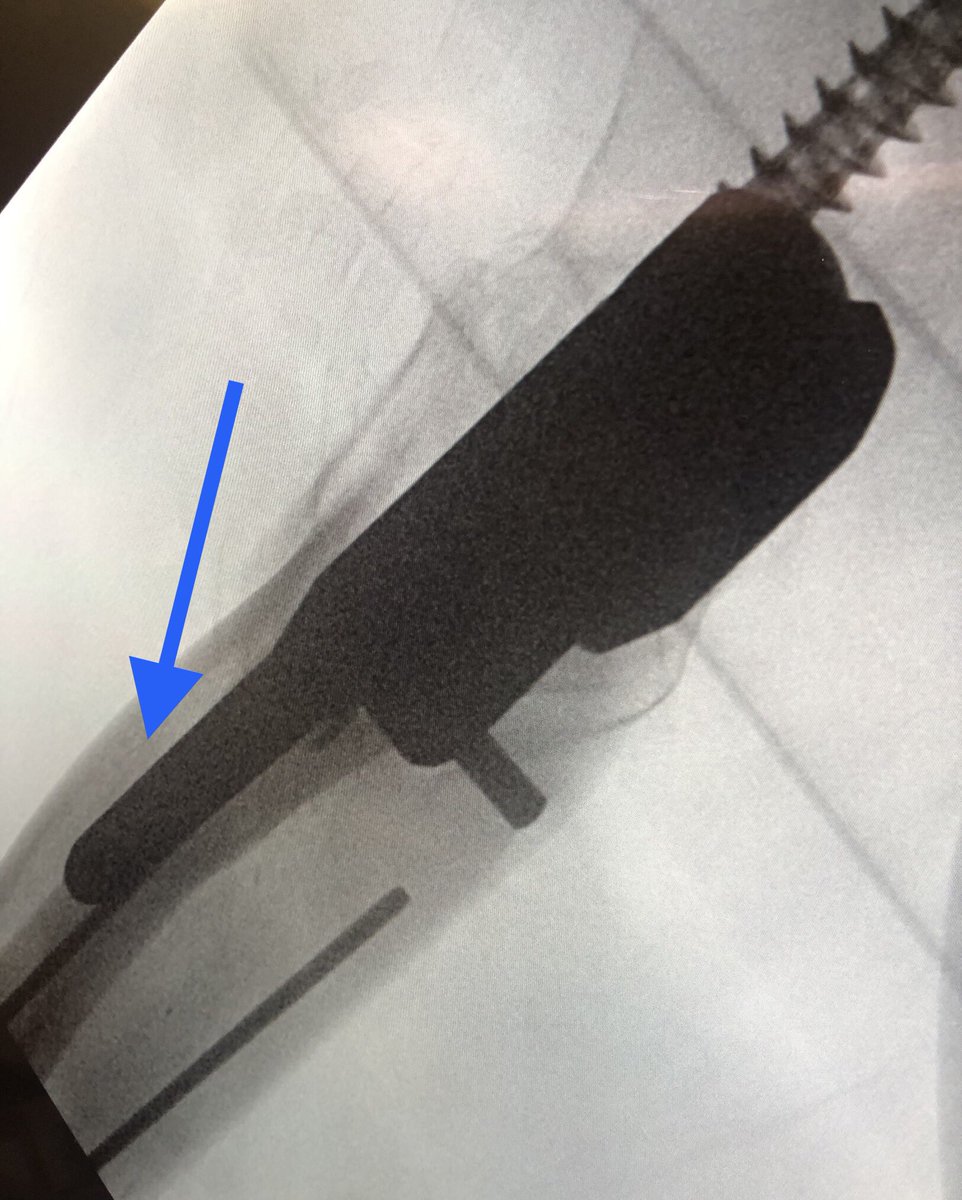

[15/18] I always try to build in some compression. The place to watch is the inferior medial portion of the fracture (arrow). Don’t overdo it or the nail starts to migrate medially.